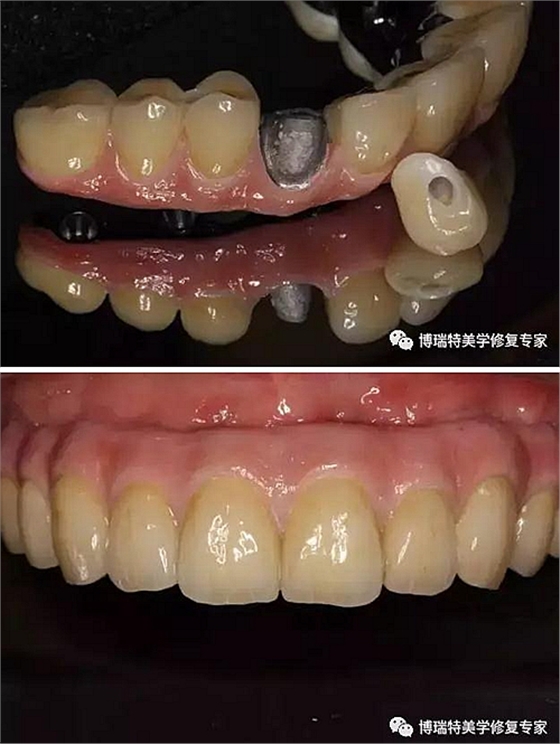

使用螺絲固位基臺手柄安裝螺絲固位基臺,先直基臺后角度基臺;直基臺通過手柄安放,使用工具盒中的球形基臺螺絲刀旋緊至25Ncm;角度基臺通過手柄選擇合適的角度(手柄和直基臺盡量保持平行),然后通過六角螺絲刀安裝中央螺絲,旋緊到25Ncm;

安裝臨時基臺;

口內(nèi)在臨時基臺上固定臨時義齒;

取下臨時基臺和臨時義齒口外調(diào)磨修整;

患者口內(nèi)安裝臨時義齒,完成即刻修復;